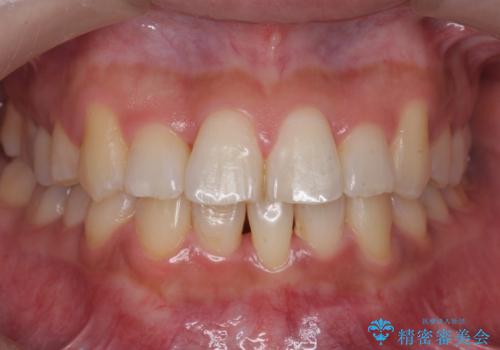

- 前歯のがたつき、受け口を主訴に来院。

上の前歯が二本裏側に入っていました。(反対咬合といいます)

上はワイヤー部分矯正、下はインビザライン(マウスピース)で部分矯正を行いました。

下の前歯を内側に入れる為、一本抜歯しています。

上の前歯のデコボコは激しく、かぶせ物で治療するとなると2本抜歯してブリッジになってしまいます。ダミーの歯の大きさも小さくなるため不自然になり下の歯のがたつきもあるためお勧めできません。

全体矯正で治そうとすると非抜歯ですとだいぶ口元が前に突出するのに加え、下の前歯が入りきらない可能性がありました。上下左右4本抜歯となるため、それを回避するのに下の前歯を1本抜歯して、下の前歯を確実に内側に入れています。